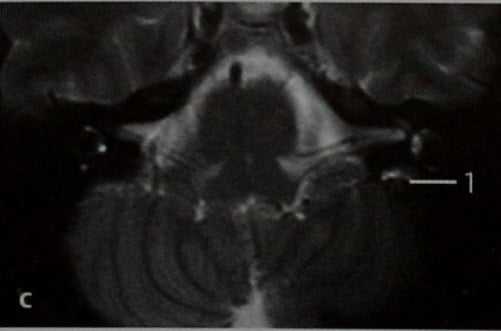

МРТ: Т2-взвешенное изображение в горизонтальной проекции. Опухоли на МРТ соответствует зона повышенной интенсивности сигнала в заднемедиальной части височной кости (1) кзади от заднего полукружного канала с нормальным сигналом от содержащейся в нем жидкости, что подтверждает результат КТ.